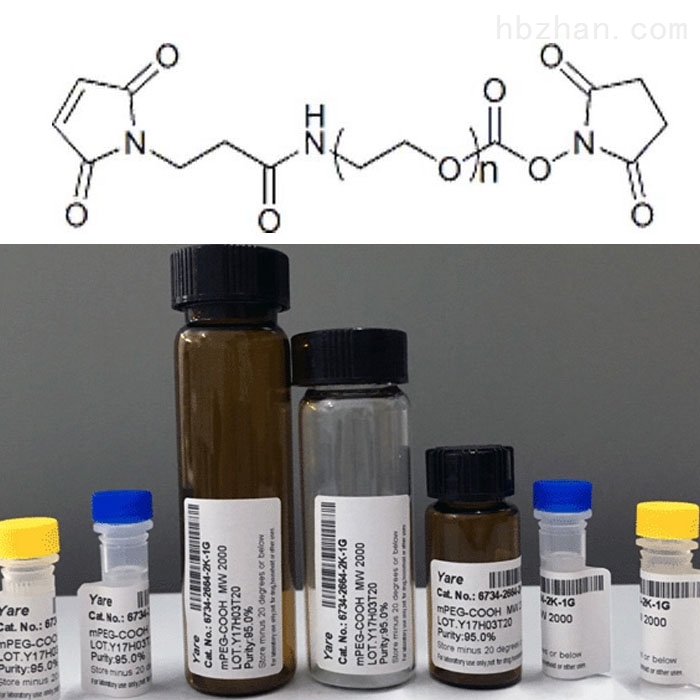

Endo BCN PEG23 BCN endo PurePEG

PEG 8 Ingredient INCIGuide

Poly Ethylene Glycol PEG Based Hydrogels For Drug Delivery In Cancer

High Molecular Weight Polyethylene Glycol PEG Sanyo Chemical

High Molecular Weight Polyethylene Glycol PEG Sanyo Chemical